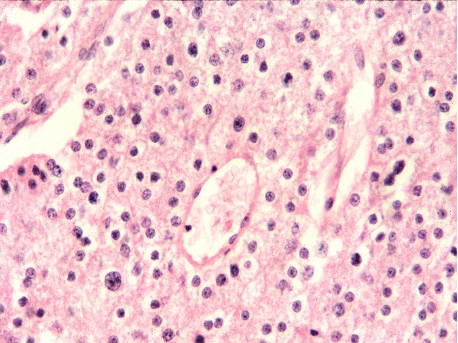

Figs 1 and 2 from a mass in the right hypochondriac region.

Make your diagnosis.

Fig 1 : Giemsa x 100

Fig 2 : Giemsa x 400